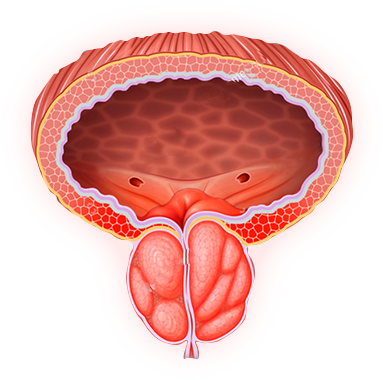

La Chancapiedra es una planta tradicional amazónica con filantósidos y lignanos que relajan la musculatura lisa del tracto urinario, facilitan la micción y apoyan la prevención de cálculos renales. Su acción complementa el efecto descongestivo sobre la próstata agrandada.